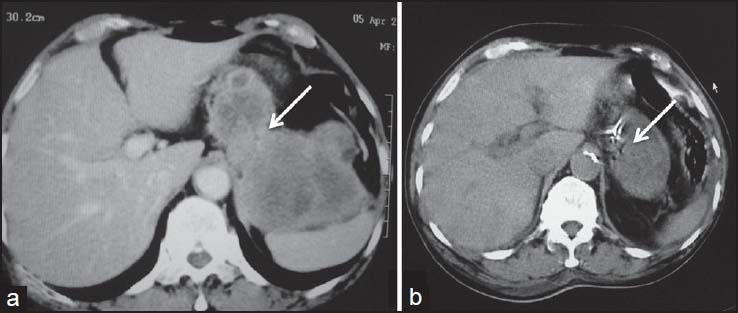

Complete surgical excision is the treatment of choice. Unlike carcinomas, resection of GISTs does not require wide bowel excision or lymphadenectomy as these tumors usually do not show lymph node metastases.[8] However, despite apparently complete resection with clear margins, the recurrence rate is high. Chemotherapy with imatinib mesylate, a tyrosine kinase inhibitor has been found to be highly effective in treatment of metastatic GIST. Imatinib mesylate has revolutionized the management of GIST. Now it is often used as the first-line treatment for unresectable, metastatic, or recurrent GIST. Although complete responses are rare, a large majority of patients with metastatic or inoperable GIST have either a partial response or disease stabilization after starting imatinib. Median survival rates have gone from <2>5 years since the advent of imatinib therapy.[11] Role of imaging also lies in response evaluation of patients treated with imatinib. Response to imatinib is characterized by decreased enhancement, resolution of the enhancing tumor nodules and a decrease in tumor neovascularity [Figures [Figures1616--20].20]. These changes are usually seen within 1-month of initiation of chemotherapy. Initially, tumors may enlarge during treatment due to intratumoral hemorrhage and myxoid degeneration. Enlargement with an overall decrease in tumor enhancement suggests a favorable response. Presence of new enhancing nodules within the tumor is consistent with recurrence.[12]

| Figure 16:Malignant metastatic stomach gastrointestinal stromal tumors posttreatment — (a) Axial noncontrast computed tomography scan showing heterogeneous mass arising from stomach and abutting the liver (b) posttreatment the mass shows heterogeneous enhancement with significant decrease in size

| Figure 16:Malignant metastatic stomach gastrointestinal stromal tumors posttreatment — (a) Axial noncontrast computed tomography scan showing heterogeneous mass arising from stomach and abutting the liver (b) posttreatment the mass shows heterogeneous enhancement with significant decrease in size